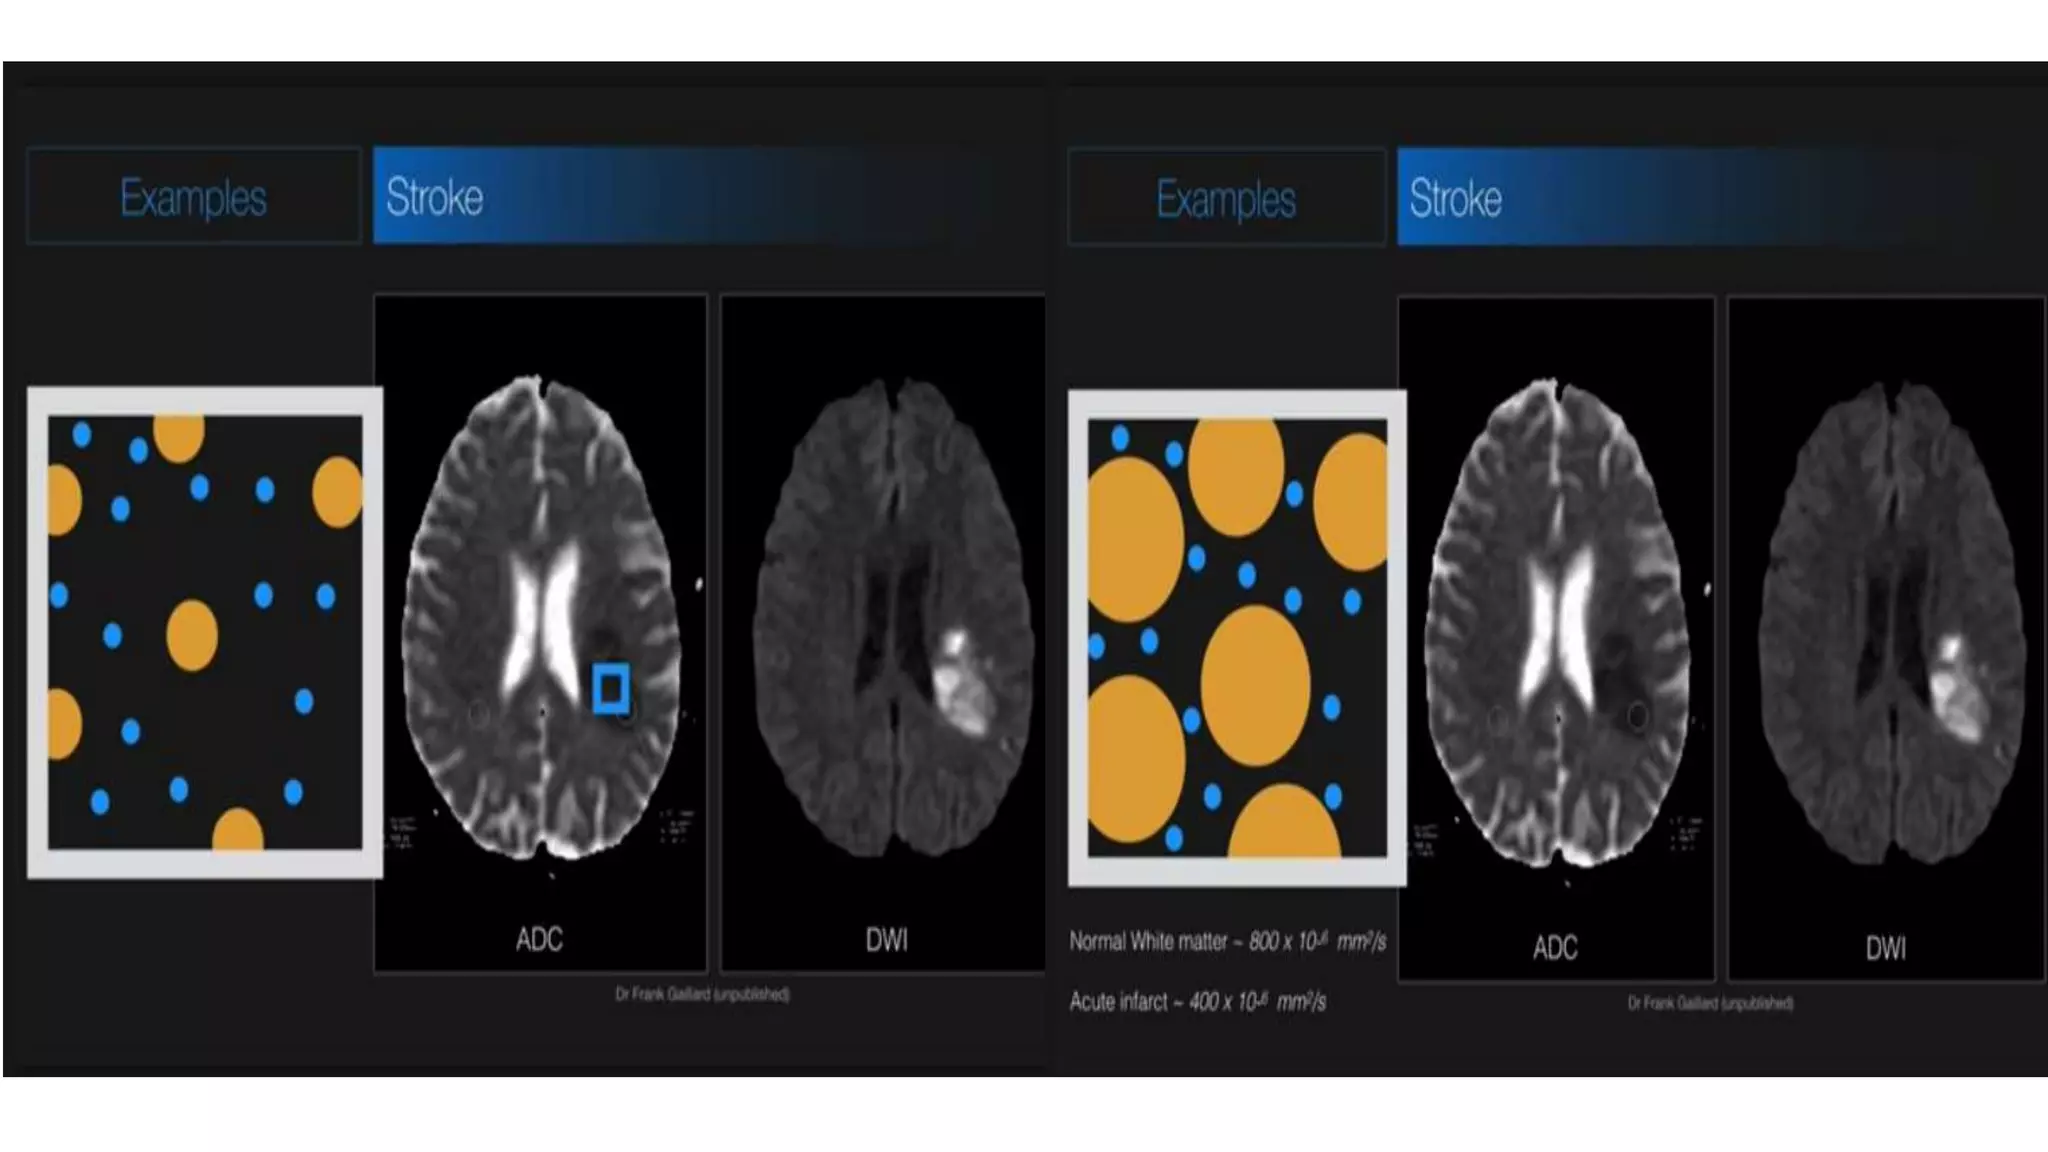

CLINICAL APPLICATIONS OF DWI

NEUROIMAGING applications :

1. Stroke

2. Epidermoid vs arachnoid cyst

3. Abscess vs simple cystic lesion

4. DWI in brain tumors

DWI in BODY IMAGING:

MR PERFUSION in STROKE

• DWI & PWI together are very

effective in detection of early

ischemia.

• The mismatch between PW &

DW represents potentially

salvageable tissue(PENUMBRA).

• Small mismatch has a good

outcome.